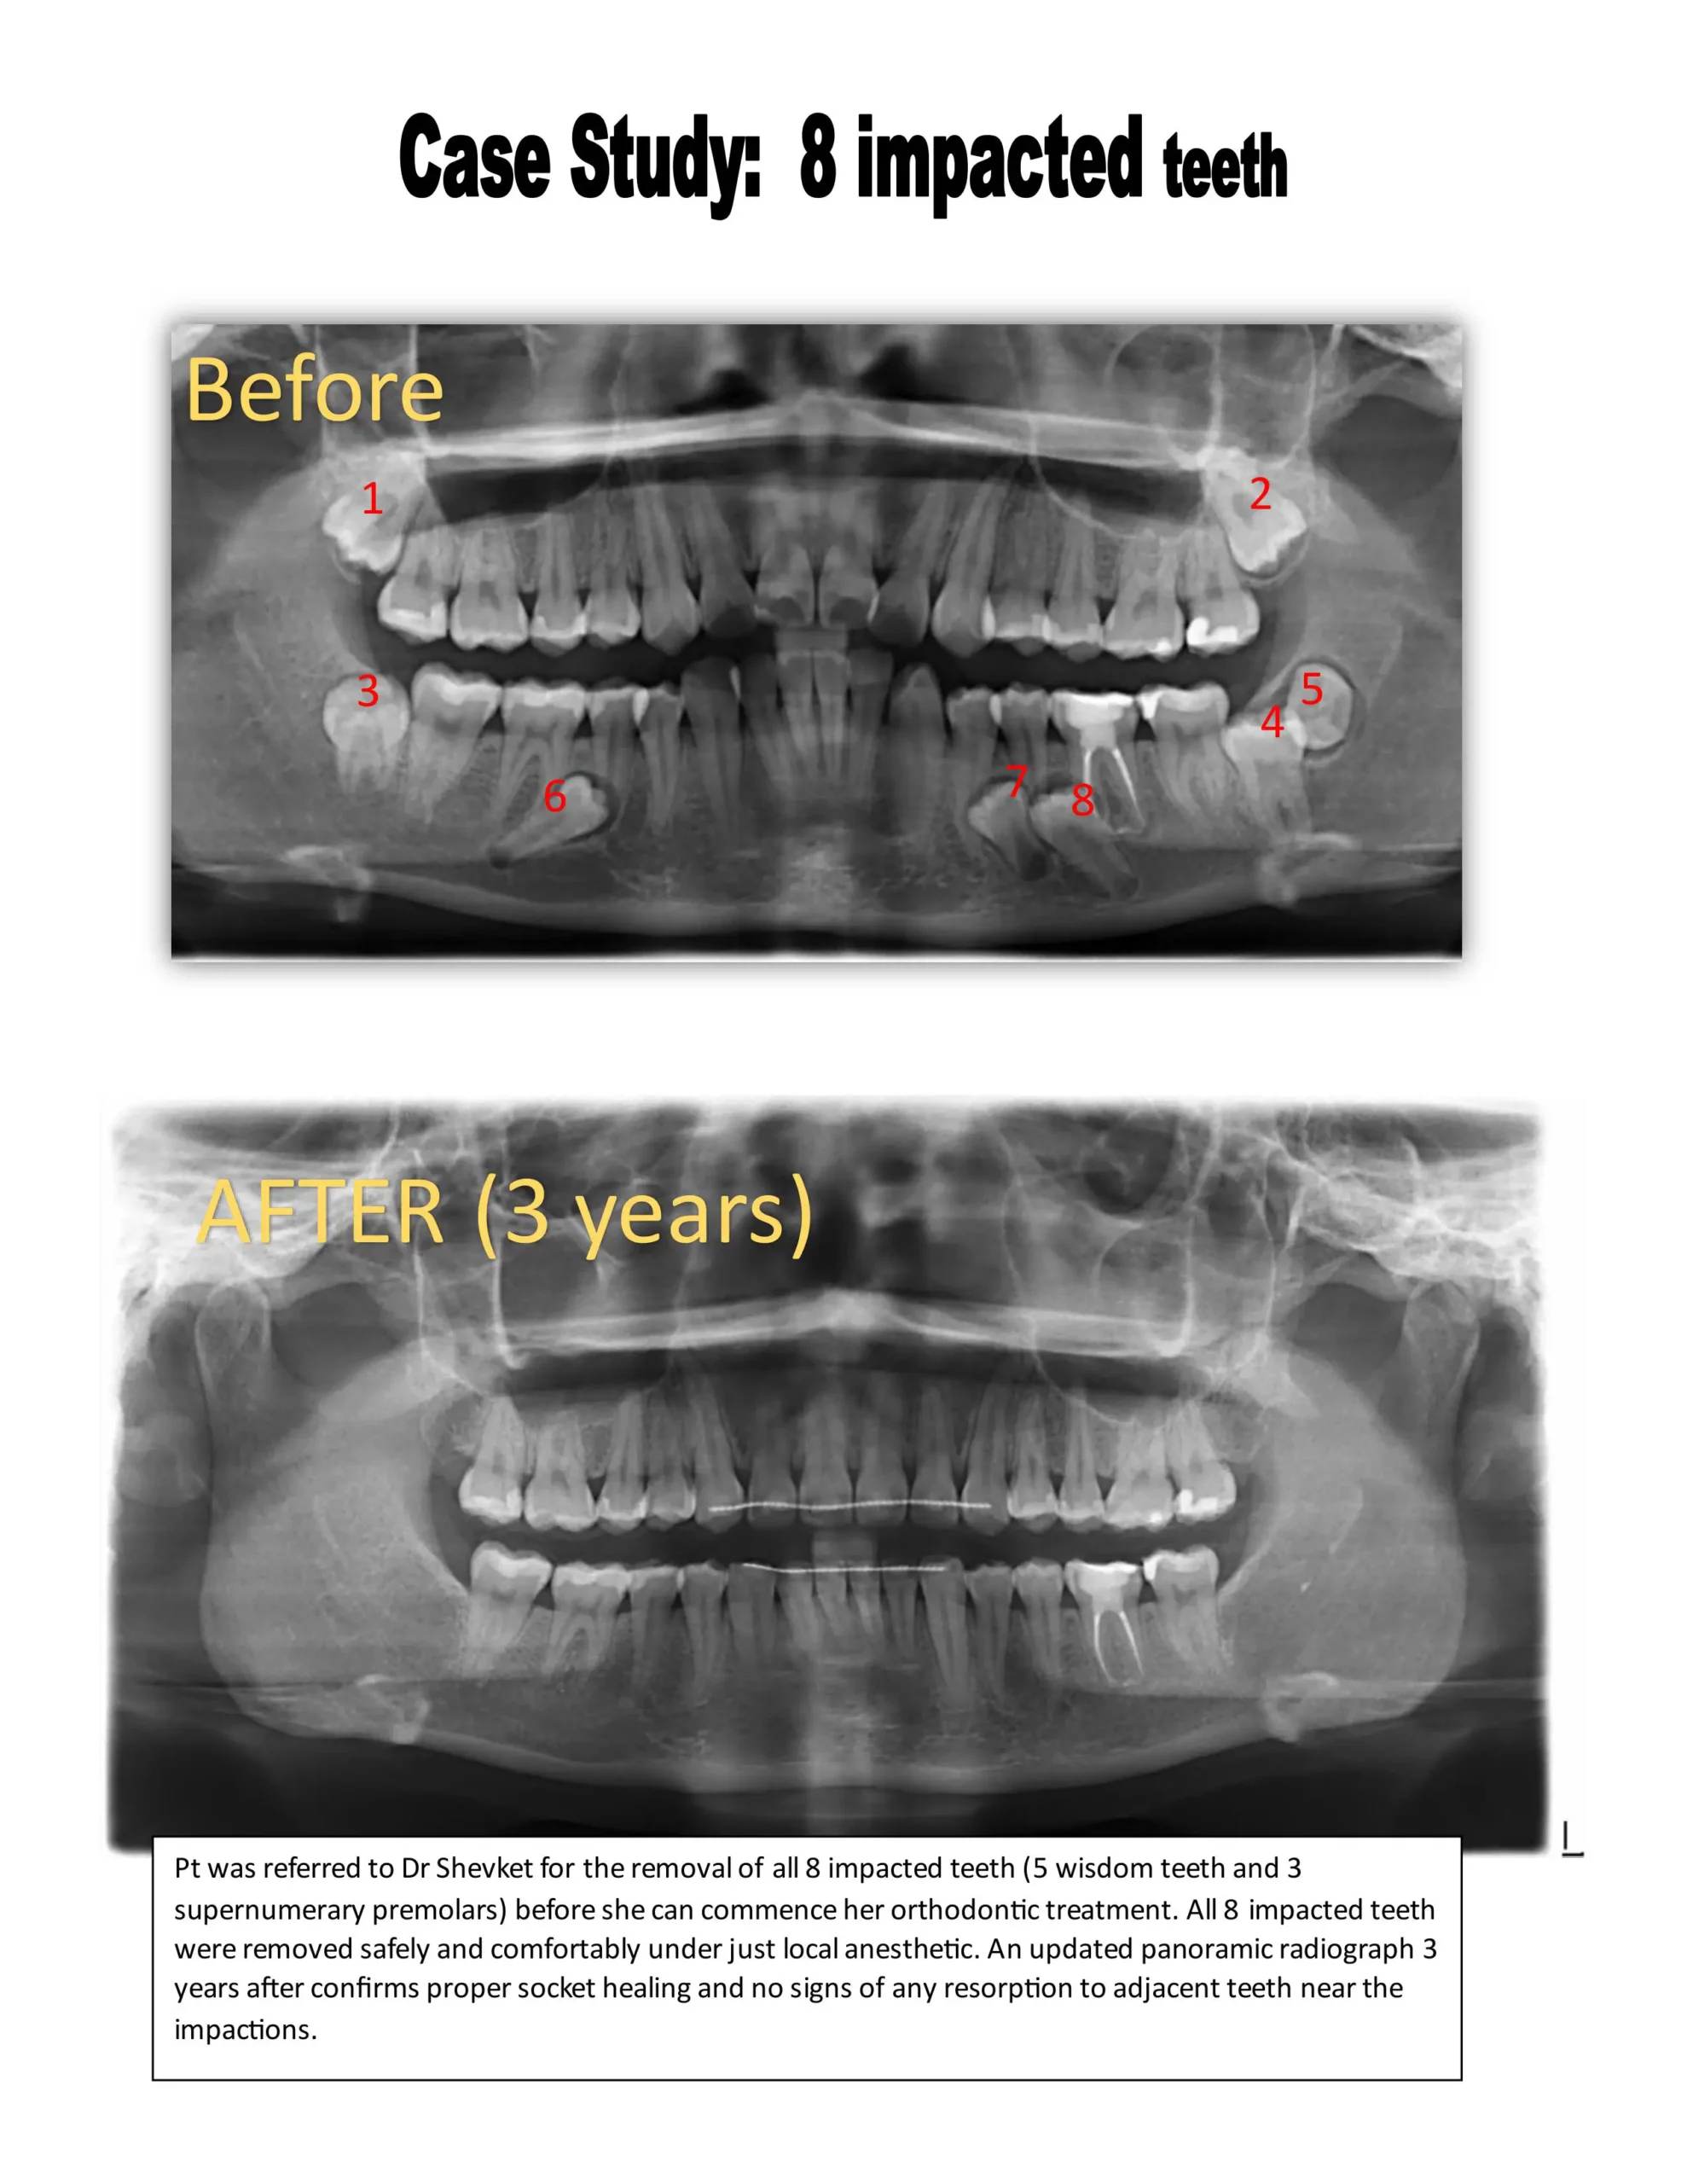

Let Dr. Shevket evaluate your case, and he will give you his professional opinion whether your wisdom teeth are impacted, and require extraction. BOOK a complimentary consultation now – TEXT OR EMAIL